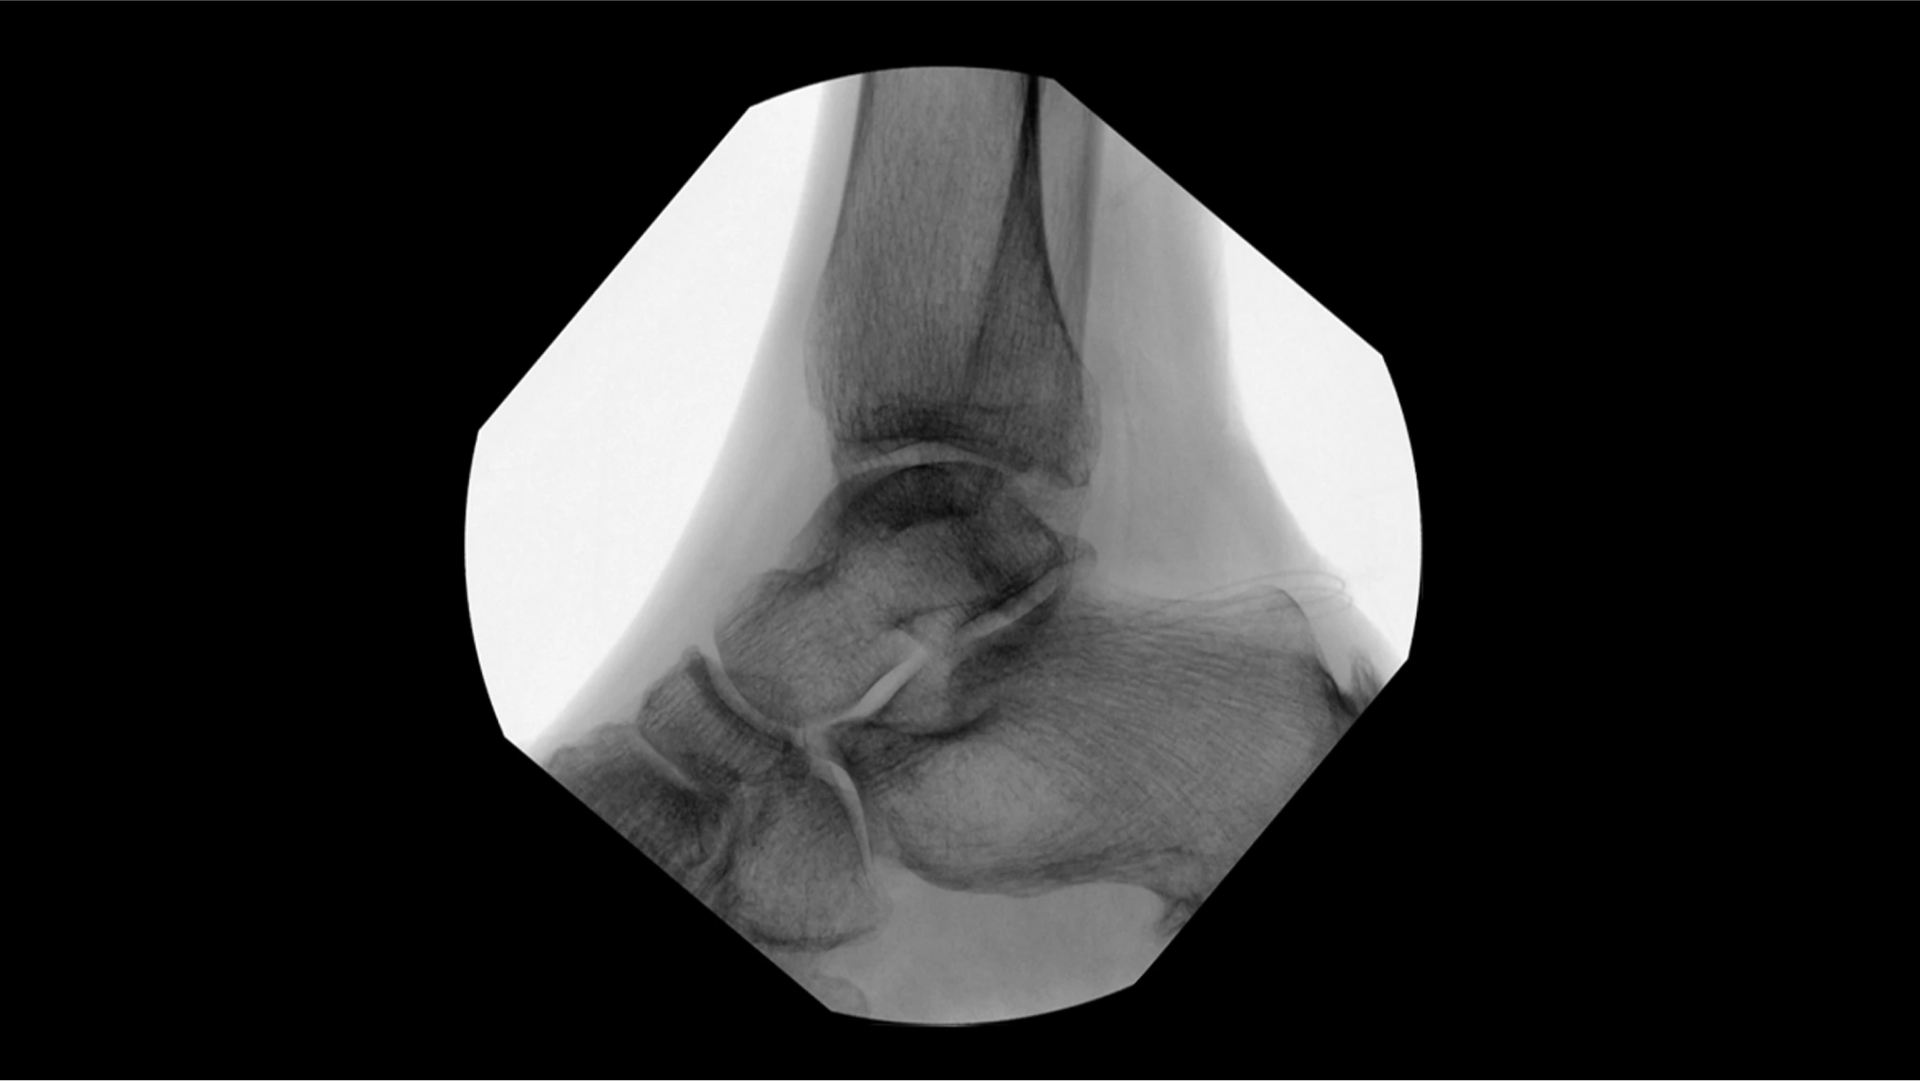

Visualizing small details such as bone fragments as well as assessing anatomical joint alignment is critical to increase clinical confidence during extremity imaging. With an OEC C-arm see clear, large images that enable you to accelerate clinical decisions and streamline your workflow during surgical procedures.

Increase clinical confidence by visualizing small details; such as bone fragments as well as assessing anatomical joint alignment with modern imaging tools such as Live Zoom, Digital Pen, and Fluorostore

Complex extremity procedures require powerful imaging systems. OEC premium C-arms perform imaging in a variety of procedures such as:

• Fracture reduction

• Distal radius fracture